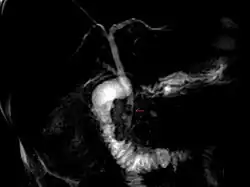

Coledocolitíase é a presença de cálculos no ducto colédoco. Esta condição causa icterícia e lesão às células do fígado, sendo uma emergência médica, necessitando de CPRE ou tratamento cirúrgico.

Entretanto, um ultrassom demonstrando um ducto colédoco aumentado é o exame de escolha.